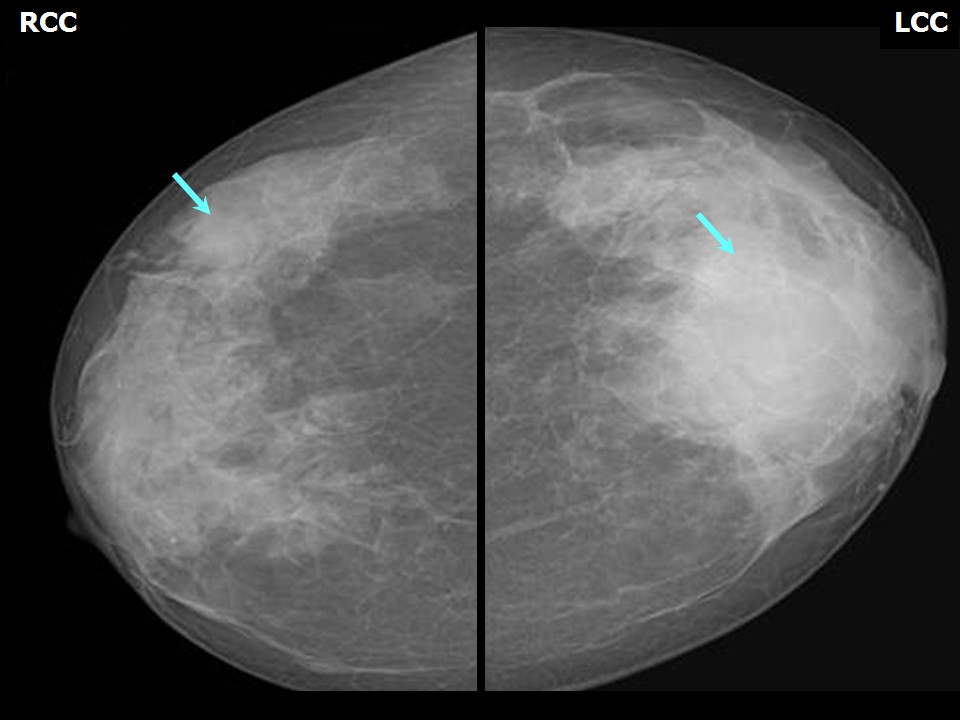

Что такое маммография: важность, процесс и результаты